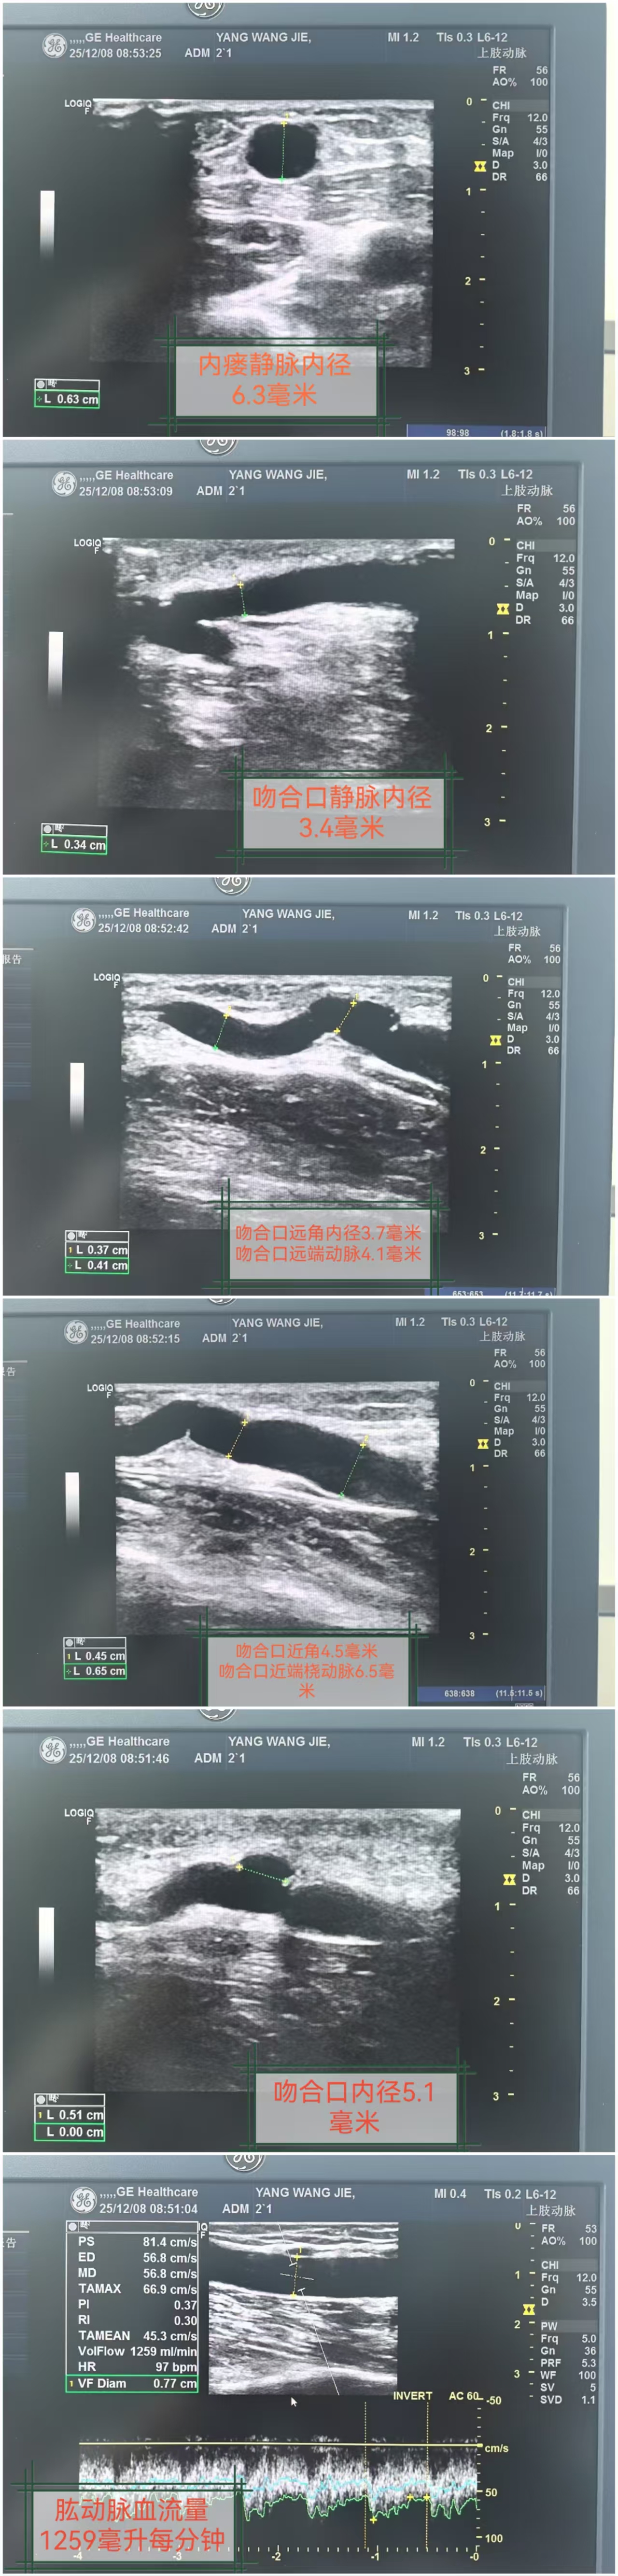

Preoperative vascular ultrasound evaluation | /uploads/patrecord/11788/param512688/0cfc36ca-62a6-4d04-a620-284df966f777.jpg |